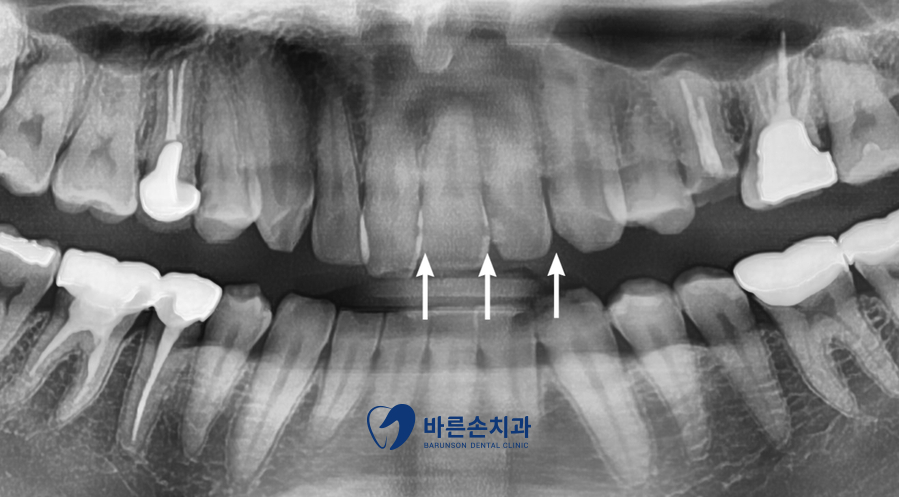

정확한 진단을 위해 파노라마 촬영을 하였습니다

파노라마 판독 결과 위 앞니 사이에 충치가 있는 게 보이네요

아직까지는 초기 충치 단계로 보여

레진 치료로 결정하였습니다